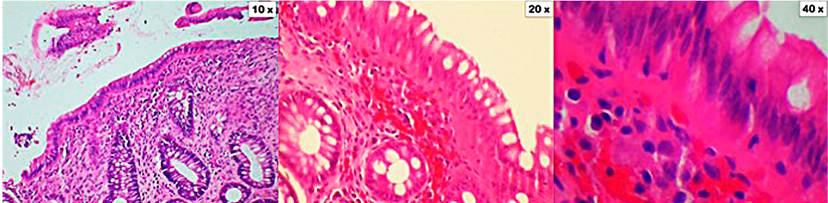

Figure 3 Collagenous colitis. The cuts show the mucosa of the colon distorted by the presence of a thickened subepithelial collagen band. Also, there are focal entrapment of capillaries, red blood cells, and inflammatory cells. In the lamina propria, there is a significant inflammatory infiltrate composed of lymphocytes, plasma cells, and eosinophils (10x, 20x, and 40x magnification). Coloration of hematoxylin and eosin (H&E).